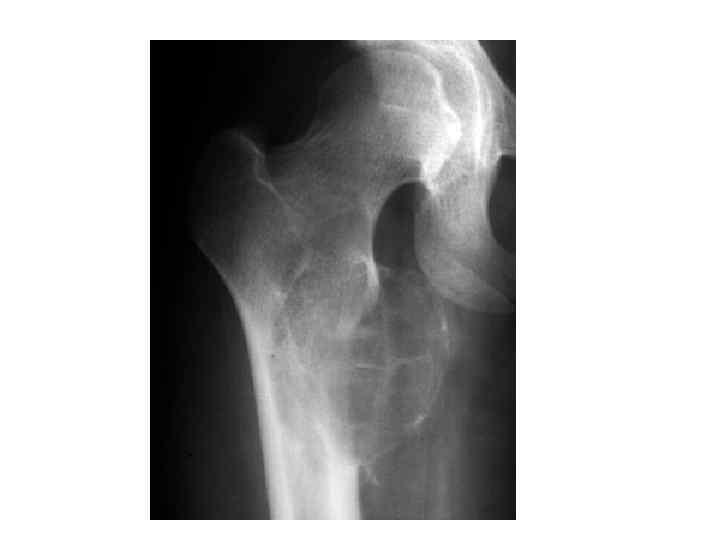

На рентгенограмме проксимальных отделов левой бедренной кости в задней проекции определяется: в медиальной части подвертельной зоны бедренной кости деформация её в виде вздутия за счет наличия здесь неправильноокруглой формы литического образования с четкими наружными контурами, разделенного на несколько крупных ячеек, размером 6, 0 на 4, 0 см. Кортикальный слой по периферии образования значительно истончен, но прослеживается на всем протяжении. • Деструктивных и периостальных изменений не отмечается. Соседние участки кости не изменены. Заключение: учитывая локализацию образования, его скиалогический характер данные за аневризматическую костную кисту. Вместе с тем нельзя полностью исключить возможности изолированной костной кисты. •